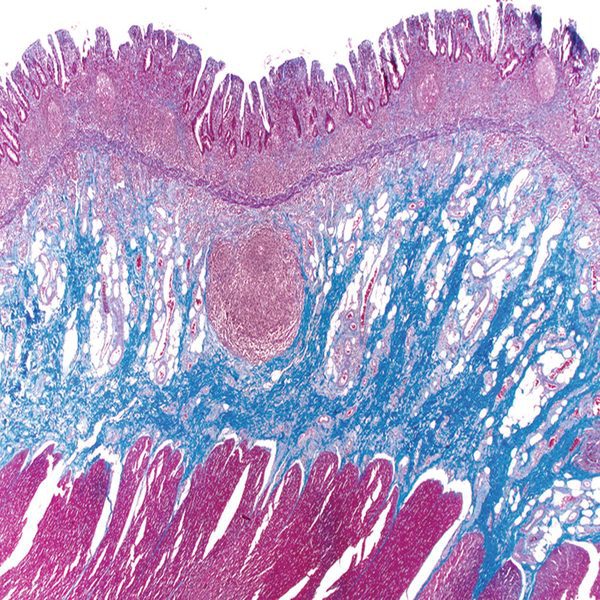

- General and specialized tissue and cell staining

- Preparation of sections from chemical and natural tissue scaffolds

Histological methods includes sample processing in the pathology laboratory, preparation of the slide and its examination under a microscope, sample fixation, molding, microtome cutting, staining and assembly of the slides.

On the other hand, in cutting-edge sciences such as tissue engineering, the use of up-to-date techniques for section preparation and cell tracking and engineered tissue structure has contributed significantly to the development of new studies.